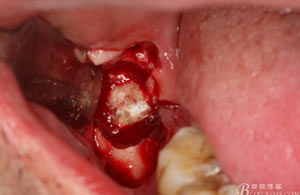

圖1。術(shù)前檢查的口內(nèi)像:48區(qū)域的位置有一瘺口。捫診溢膿。48未萌出。

圖6.行角形瓣切開、翻瓣、暴露骨面,可見48牙冠表面有炎性肉芽組織